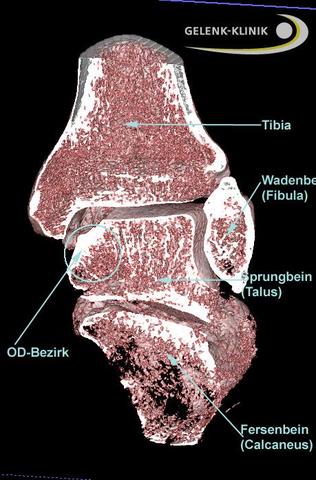

Digitale Volumentomographie (DVT) zur Diagnostik und OP-Planung bei Ermüdungsbruch

Die digitale Volumentomographie (DVT) ist eine moderne bildgebende Untersuchungsmethode, die bei der Diagnose und OP-Planung eines Ermüdungsbruchs eingesetzt werden kann. Mit Hilfe des DVT können dreidimensionale Bilder des betroffenen Bereichs erstellt werden, was eine genaue Analyse der Knochenstrukturen ermöglicht.

Bei einem Ermüdungsbruch zeigt sich in den DVT-Bildern typischerweise ein Knochenödem, also eine Wassereinlagerung im Knochen. Dieses Ödem ist ein Hinweis auf die Stressreaktion des Knochens auf die Überlastung. Zudem können auch sichtbare Frakturlinien oder andere strukturelle Veränderungen am Knochen erkannt werden.

Die DVT ist besonders vorteilhaft, da sie im Gegensatz zu herkömmlichen Röntgenaufnahmen oder CT-Scans eine geringere Strahlenbelastung für den Patienten bedeutet. Zudem liefert sie detailliertere Bilder als das konventionelle Röntgen.

Die Ergebnisse der DVT-Bilder helfen dem Fußspezialisten bei der Planung einer möglichen Operation. In einigen Fällen kann es notwendig sein, den Ermüdungsbruch operativ zu behandeln, zum Beispiel wenn der Bruch nicht von alleine heilt oder wenn eine Stabilisierung des Knochens erforderlich ist.

Die digitale Volumentomographie ist somit eine wertvolle Methode zur Diagnosestellung und Behandlungsplanung bei einem Ermüdungsbruch im Fuß. Sie ermöglicht eine genaue Analyse der Knochenstrukturen und hilft dem Fußspezialisten bei der Entscheidung über die geeignete Behandlungsmethode.

Das ZFSmax verfügt über modernste Diagnoseverfahren wie die Digitale Volumentomographie (DVT), um einen Ermüdungsbruch genau zu identifizieren und eine genaue OP-Planung durchzuführen. Diese bildgebenden Untersuchungen zeigen typische Veränderungen am Mittelfuß, die auf einen Ermüdungsbruch hinweisen.